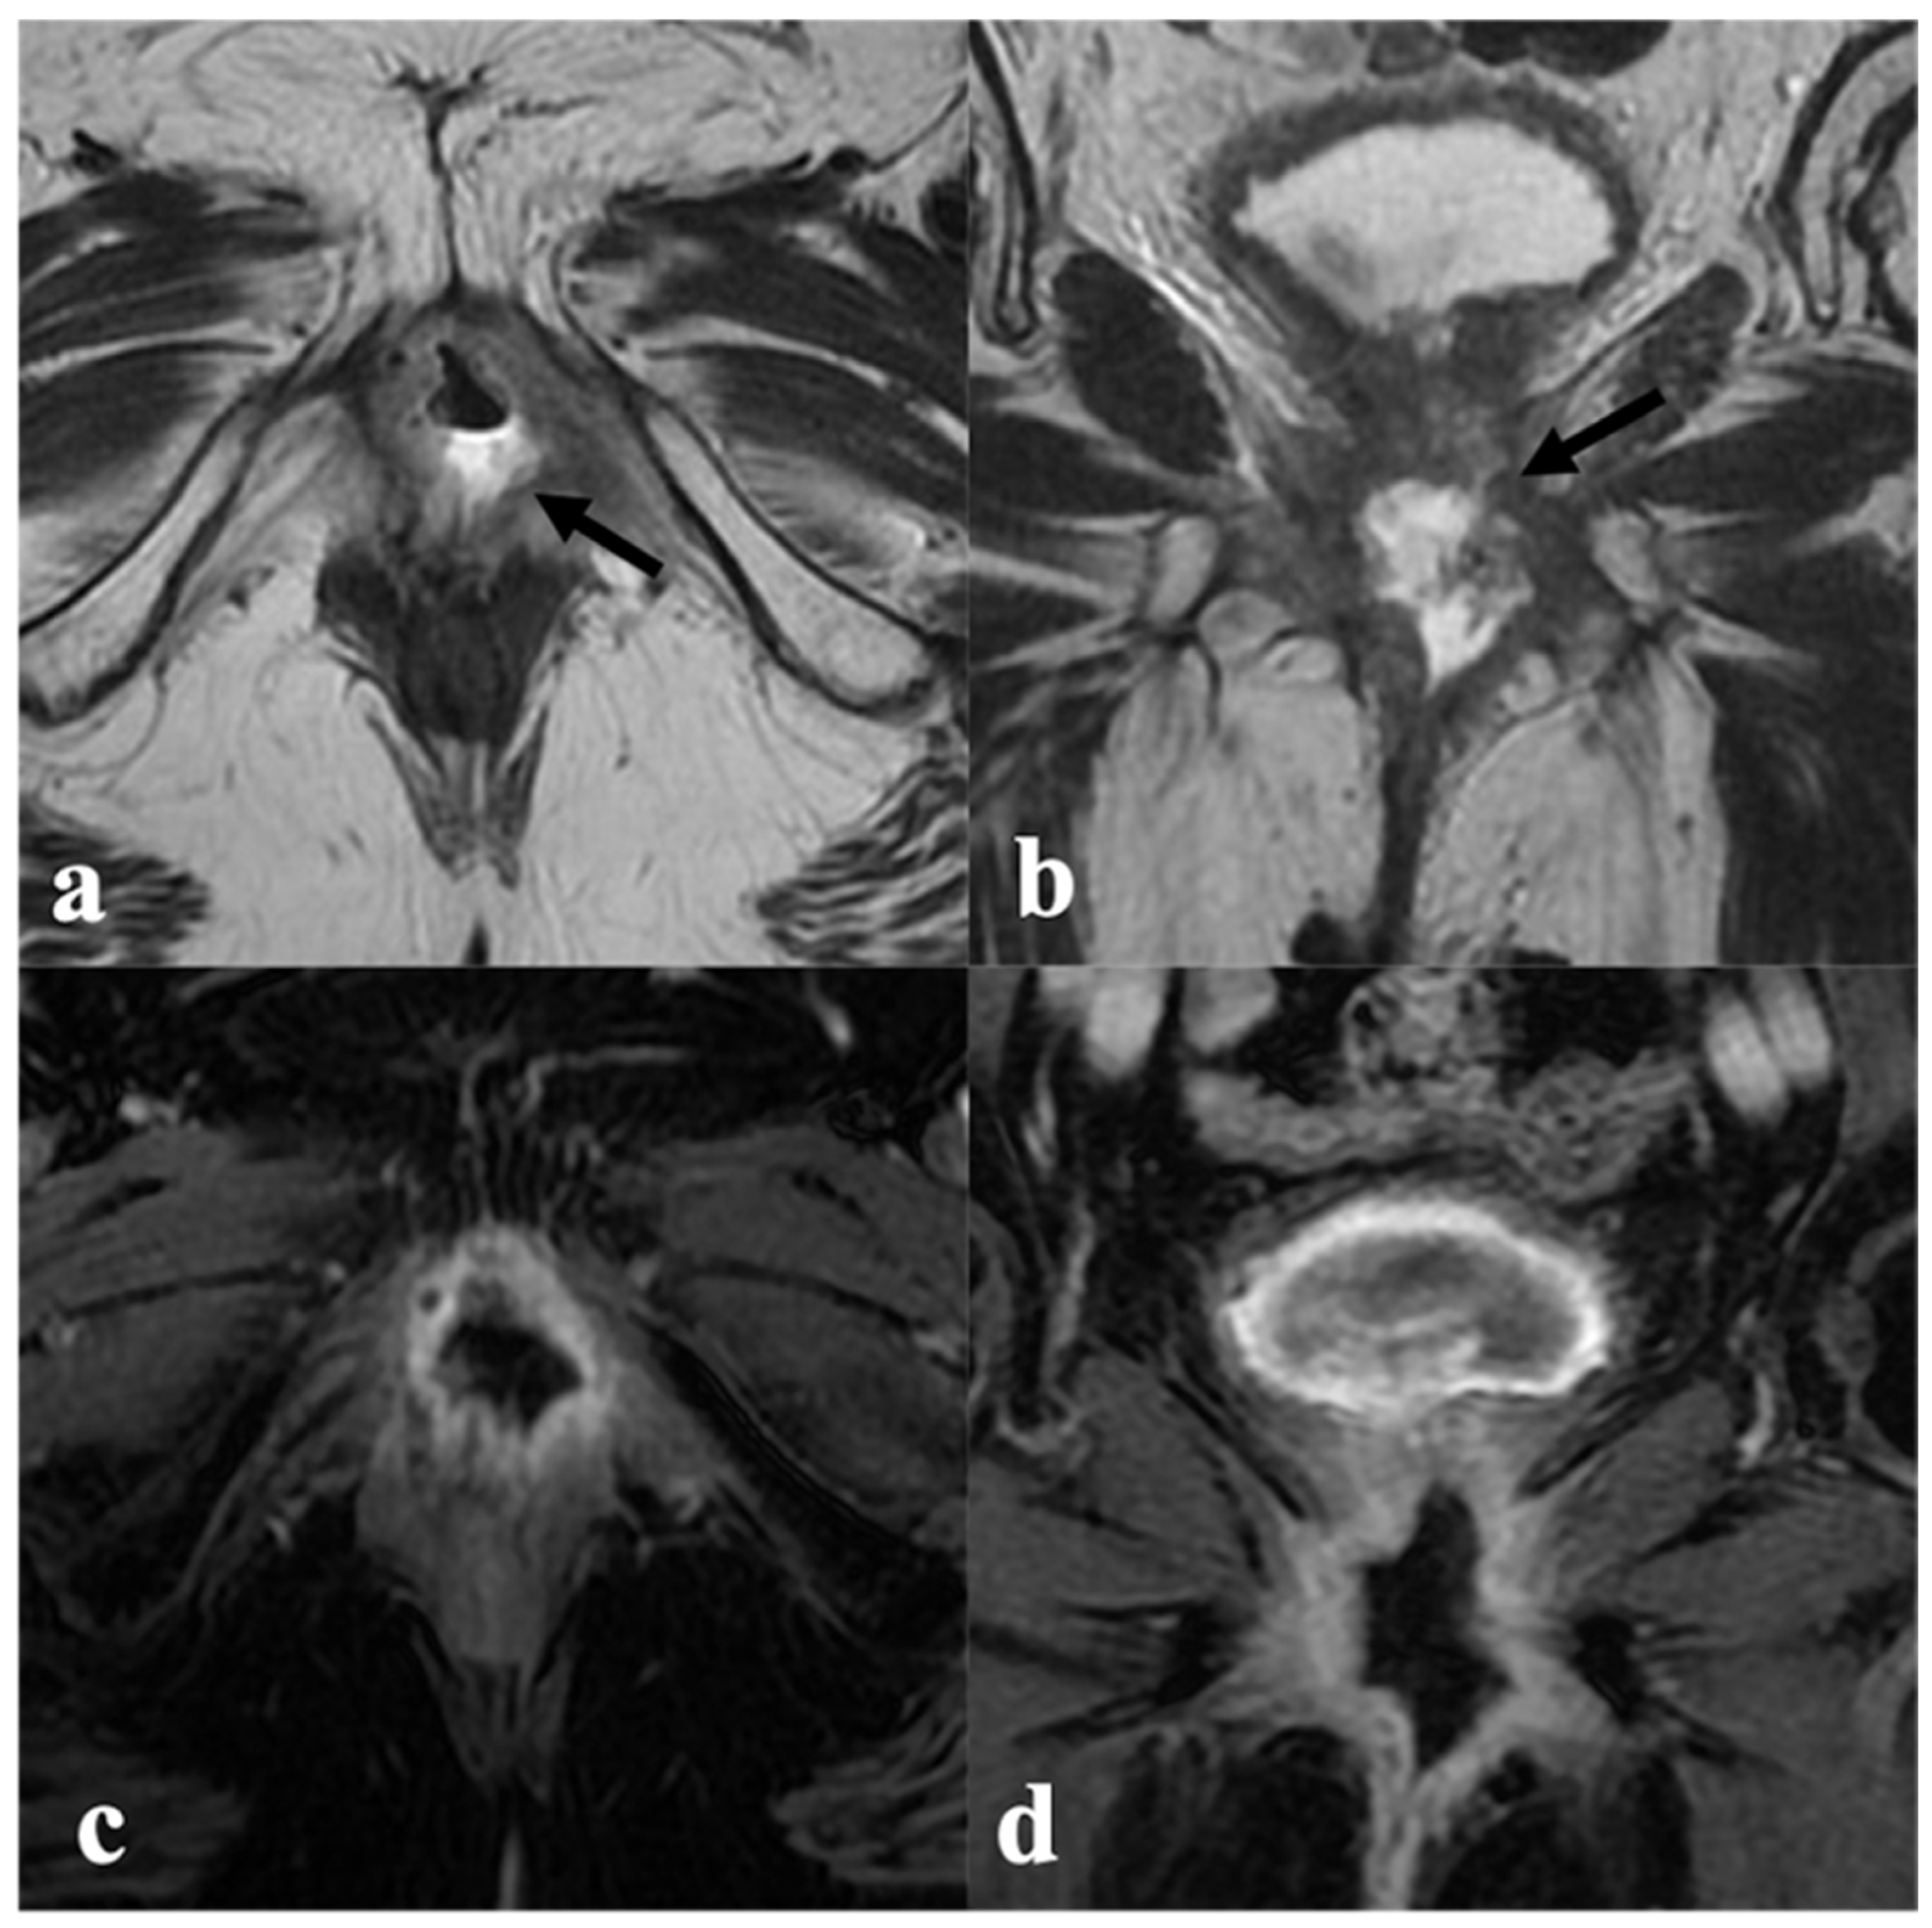

4. Post-CRT MRI Findings

4.1. Local Tumor Status and Residual Invasion of Adjacent Organs

4.2. Lymph Node Status